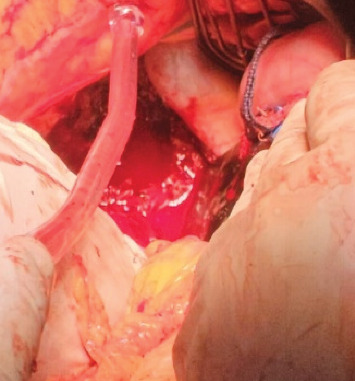

简介:原发性肝异位妊娠罕见;据报道,每次子宫妊娠的发病率约为1:15 000。本研究旨在探讨肝异位妊娠的临床表现及治疗方法。病例介绍:我们提出的情况下,病人没有怀孕史谁提出腹痛难治性治疗。人绒毛膜促性腺激素(β-hCG)水平为55,710 mIU/mL,腹部超声显示右肝叶水平出现50 mm × 50 mm的圆形图像,并发低血容量性休克。在诊断为腹部异位妊娠的情况下,患者接受了手术。讨论:最初,进行了剖腹探查,发现存在出血、凝块和妊娠囊;随后,进行楔形切除,Pringle手法和肝脏填塞,在患者的病例中获得了良好的结果。结论:原发性肝性异位妊娠可通过β-hCG测定和连续腹部超声检查诊断。治疗可以是药物(甲氨蝶呤)或手术,应用技术,如品客手法。

Introduction: Primary hepatic ectopic pregnancy is rare; it has been reported to have an incidence of 1:15,000 per uterine pregnancy approximately. This study aims to determine the clinical presentation and treatment of hepatic ectopic pregnancy. Presentation of Case: We present the case of a patient with no history of pregnancy who presented with abdominal pain refractory to treatment. With a human chorionic gonadotropin hormone (β-hCG) measure of 55,710 mIU/mL, an abdominal ultrasound that revealed the presence of a rounded image of 50 mm × 50 mm at the level of the right hepatic lobe and the complication of hypovolemic shock. Under the diagnosis of an abdominal ectopic pregnancy, the patient underwent surgery. Discussion: Initially, an exploratory laparotomy was performed, which revealed the presence of bleeding, clots, and a gestational sac; subsequently, a wedge resection was done, and a Pringle maneuver and hepatic packing were performed, obtaining favorable results in the patient's case. Conclusion: The diagnosis of primary hepatic ectopic pregnancy is made through β-hCG measurement and serial abdominal ultrasonography. Treatment can be pharmacological (methotrexate) or surgical, applying techniques such as the Pringle maneuver.